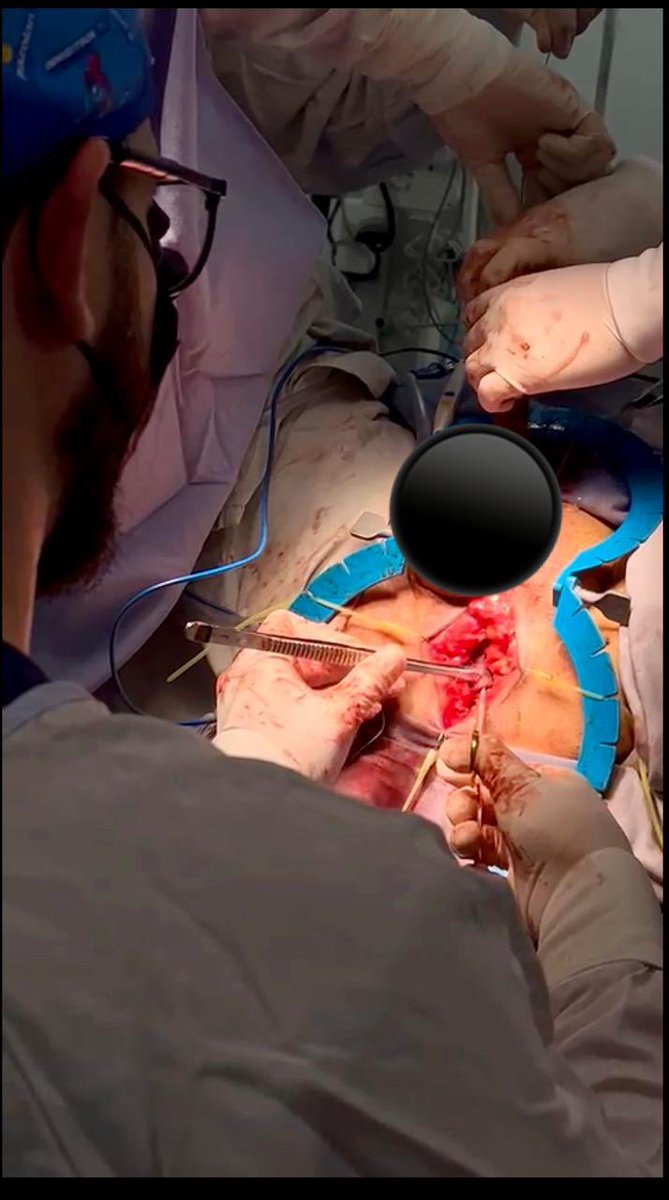

Hoy hicimos un caso interesante paciente con estenosis bulbopeneana + contractura cuello vesical y 3 UTI previas secundario a Rtup. Se realizó plastia con BMG + cervicotomia con asa de Collin’s accessndo por uretrostomia. Dr. Almeida

Hoy hicimos un caso interesante paciente con estenosis bulbopeneana + contractura cuello vesical y 3 UTI previas secundario a Rtup. Se realizó plastia con BMG + cervicotomia con asa de Collin’s accessndo por uretrostomia. <a href="/Aldolsterona/">Dr. Almeida</a>